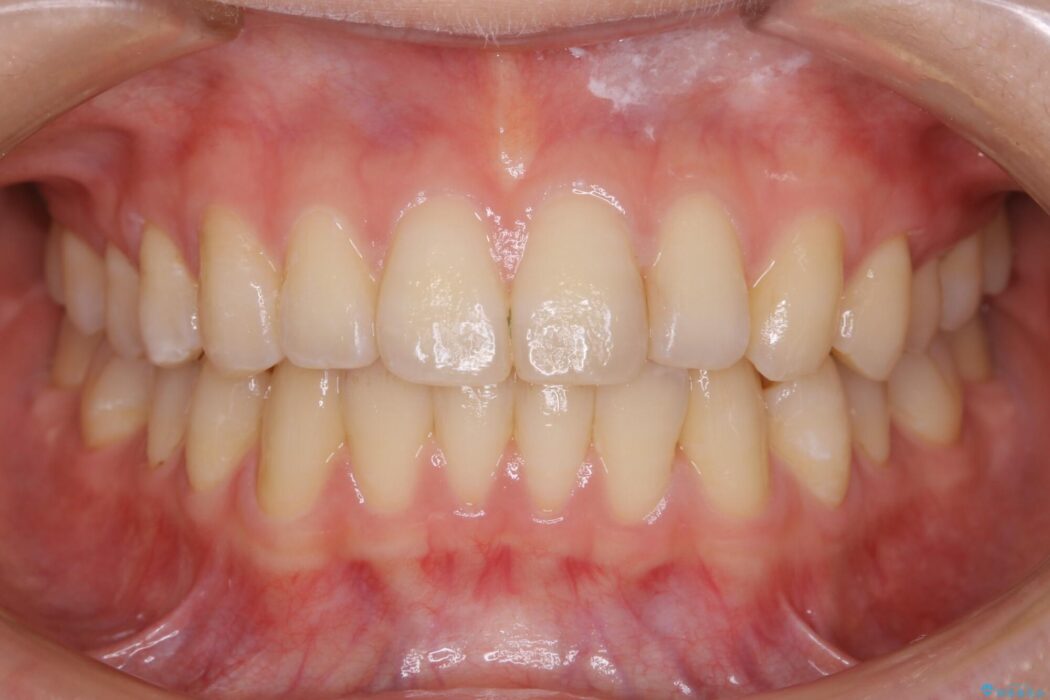

下額前歯が少しガタついていることを気にされて来院されました。

検査をしたところ奥歯の噛み合わせなどに問題が見られなかったため、軽度のねじれがある下顎前歯に焦点を当てた部分矯正の適応が可能と判断し、インビザラインのライトパッケージをご提案しました。

本症例では奥歯に関して問題がほぼ見られなかったため、部分矯正を行うことが可能と判断しました。

通常の全体矯正と比べピンポイントの部分矯正となると、動かす歯が少なくなるため治療期間が格段に短くなり、費用が抑えられることがメリットとして挙げられます。